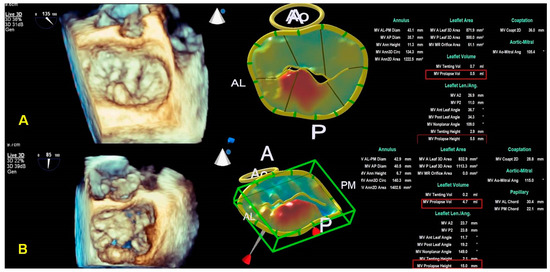

3.2. Quantification of the Morphology